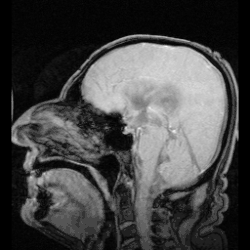

El líquido cefalorraquídeo (LCR) o líquido cerebroespinal (LCE) es un líquido incoloro que baña el encéfalo y la médula espinal. Circula por el espacio subaracnoideo, los ventrículos cerebrales y el conducto ependimario sumando un volumen de entre 100 y 150 ml, en condiciones normales.[1]

La circulación del LCE comienza en los ventrículos laterales, continúa hacia el tercer ventrículo por los agujeros de Monro (agujeros interventriculares) y luego transcurre por el acueducto cerebral (acueducto de Silvio o mesencefálico) hasta el cuarto ventrículo. Desde allí fluye, a través de un conjunto de orificios, uno central (agujero de Magendie) y dos laterales (agujeros de Luschka),[1] que ingresan en la cisterna magna, un gran depósito de líquido ubicado por detrás del bulbo raquídeo y por debajo del cerebelo y hacia abajo al conducto ependimario de la médula espinal a través del obex.

La cisterna magna se continúa con el espacio subaracnoideo que rodea todo el encéfalo y la médula espinal. Luego, casi todo el LCE fluye a través de este espacio hacia el cerebro. Desde los espacios subaracnoideos cerebrales, el líquido fluye en las múltiples vellosidades o granulaciones aracnoideas (o de Pacchioni) que se proyectan en el gran seno venoso sagital y otros senos venosos. Por último, se vacía en la sangre venosa a través de las superficies de las vellosidades.